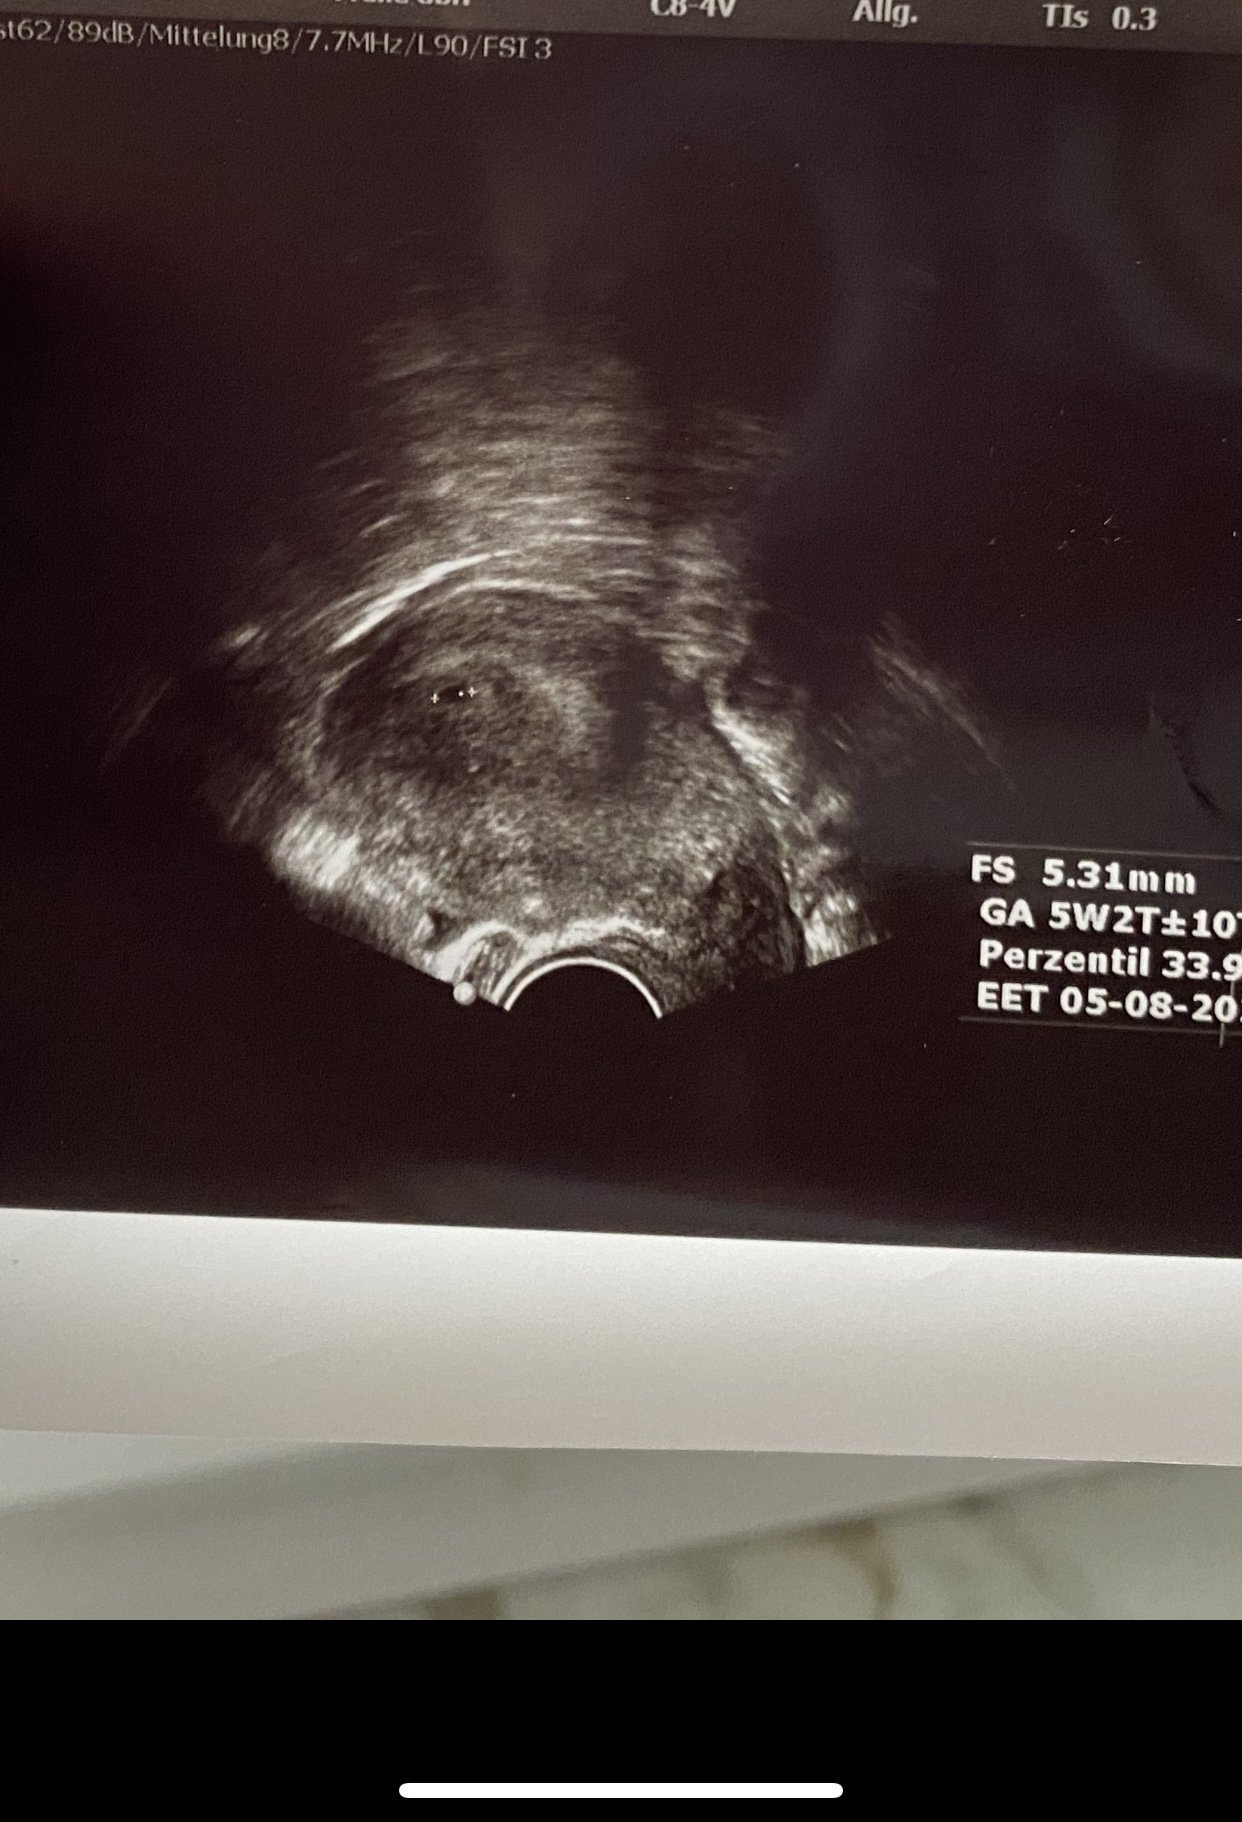

Какво представлява изображението от ехографията на 5-седмична и 2-дневна бременност?

Кога обикновено може да се види ембрионът на ултразвукова снимка?